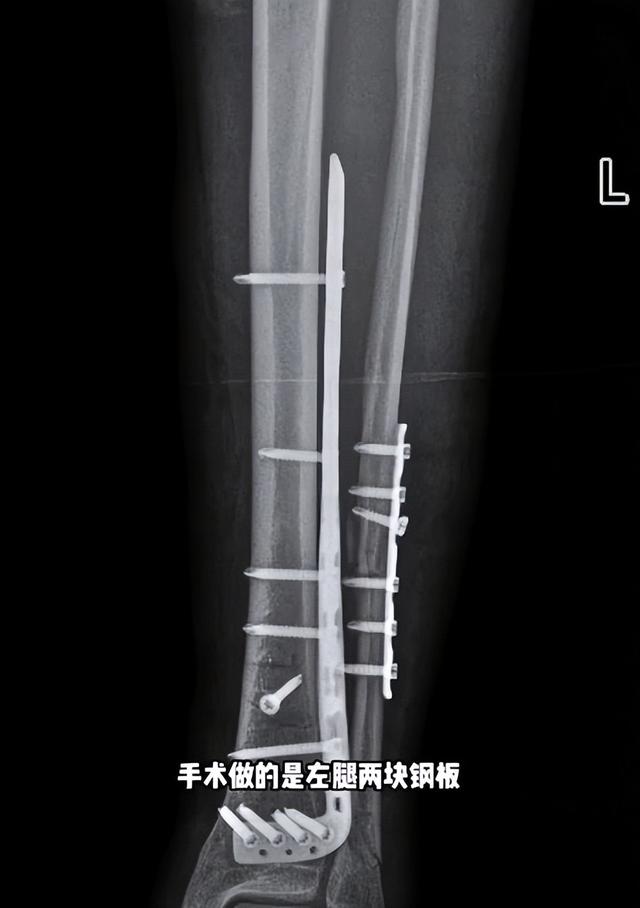

但這可是雙腿骨折手術,醫生需要在雙腿內側打上鋼釘,裝上鋼板,最後還是在全麻的條件下,手術才勉強做的。

一整天的崩潰過後,手術終於做完了。左腿加了兩塊鋼板,還有16顆釘子。右腿加了兩條髓內釘,六顆固定釘子。一共縫了45針。